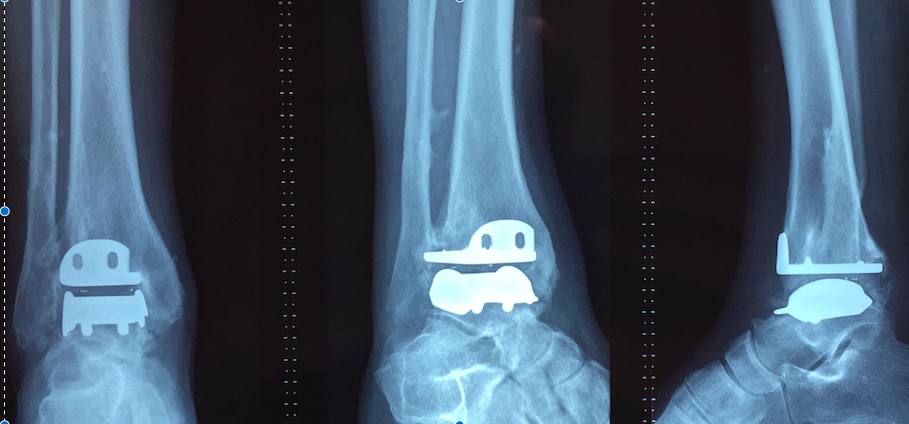

Protesis de tobillo para el tratamiento de la artrosis de tobillo en pacientes con enfermedades reumáticas o secundaria a traumatismos